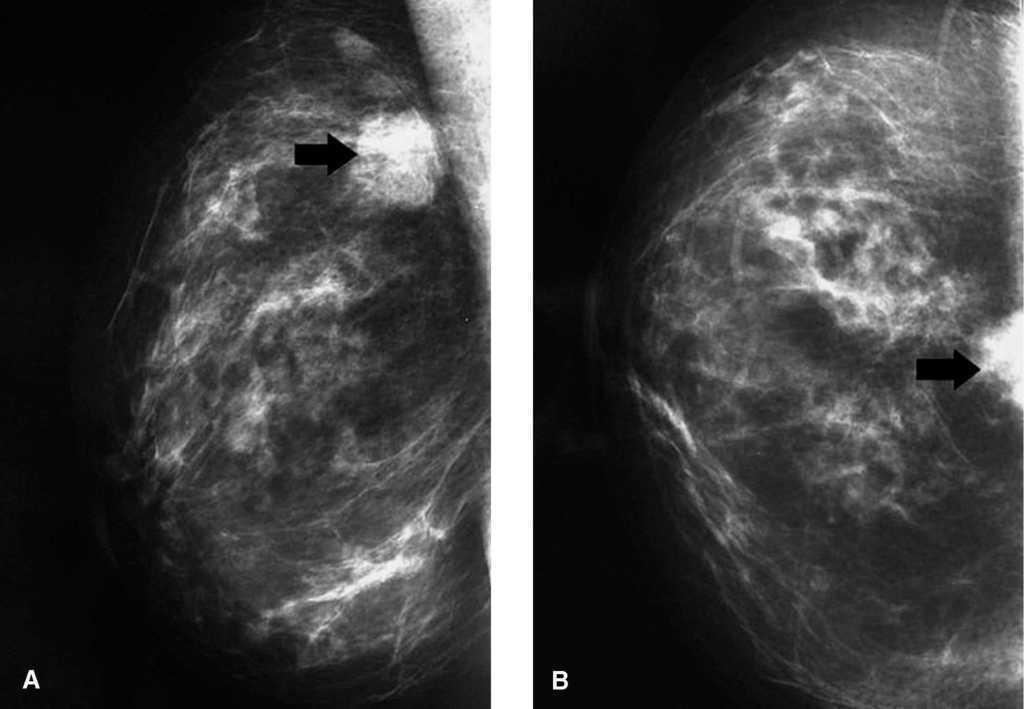

Fig.1.Mamografía derecha en la que se aprecia la lesión con características de malignidad sobre el pectoral mayor (flecha).A:proyección oblicua mediolateral.B:proyección craneocaudal.

Recientemente atendimos en nuestro servicio a una mujer de 59 años, con antecedente de mastectomía radical izquierda por cáncer a los 30 años, que presentó, en la mamografía de control contralateral, una imagen hiperdensa de nueva aparición, localizada en la línea intercuadrántica superior, de aproximadamente 2,5 cm de diámetro máximo, con características radiológicas de malignidad (fig. 1). La exploración física, mamaria y axilar era normal. En la ecografía mamaria se observó un nódulo heterogéneo mal definido, isoecoico con el parénquima, sin cavidades quísticas en su interior, indicativo de malignidad. Con la sospecha diagnóstica de cáncer de mama se realizó punción guiada con ecografía, que mostró un infiltrado linfoide. Ante la imposibilidad de diferenciar con precisión entre linfoma y seudolinfoma, se decidió efectuar una biopsia escisional de la lesión. El estudio anatomopatológico reveló una tumoración de 2,3 cm de diámetro, blanquecina, no indurada y de bordes mal definidos. En el estudio microscópico se observó un infiltrado linfoide difuso polimórfico con centros germinales involucionados y parcialmente colonizados por linfocitos maduros (figs. 2A y 2B). En el estudio inmunohistoquímico se observó que aproximadamente un 55% de la población linfoide era positiva para CD20 (fig. 2C), y el resto, para CD3 (fig. 2D) y Bcl-2. Los centros germinales involucionados resultaron ser positivos para CD23 y Bcl-6. La expresión de VS38C y cadenas ligeras kappa y lambda mostró que se trataba de una población celular politípica. El estudio molecular reveló la ausencia de reordenamiento genético monoclonal para el receptor de células T –TCR gamma, tanto para grupo III (J1, J2, J3) y grupo II (V5, V10, V11, V12) como para grupo III (J1, J2, J3) y grupo I (V2, V3, V4, V8, V9)– y también para el gen de cadenas pesadas de inmunoglobulina (IgH) –tanto FR3 y FR4 como FR2 y FR4–. Con estos hallazgos se estableció el diagnóstico de seudolinfoma mamario y se decidió la abstención terapéutica ulterior. Tras 1 año de seguimiento, la paciente se encuentra asintomática y no hay evidencia clínico-radiológica de recidiva.